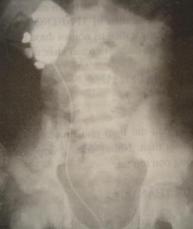

Trước bệnh cảnh đó trẻ được chẩn đoán “chấn thương thận trái trên thận trái lớn chưa rõ nguyên nhân”. Vì bệnh nhân là trẻ em, và trên lâm sàng thể chấn thương thận thuộc loại nhẹ nên được chỉ định điều trị bảo tồn nội khoa. Sau một tuần điều trị trẻ khỏe, nước tiểu nhiều và trong dần, được cho chụp UIV vào ngày thứ 10. Kết quả trên phim ghi nhận hai thận ngấm thuốc tốt, thận trái có hình ảnh đài và bể thận giãn lớn, không thấy ổ đọng thuốc, không có hình ảnh thuốc cản quang thoát ra ngoài thận. Tuy nhiên không thấy hình niệu quản trái trên phim, thận bên phải bình thường trên phim. Chẩn đoán xác định “chấn thương thận trái trên thận ứ nước bẩm sinh, khả năng do bệnh lý khúc nối bể thận – niệu quản (anomalie de la jonction pyélo-urétérale, AJPU). Sau 15 ngày điều trị trẻ được cho ra viện nhưng gia đình được dặn dò phải cho trẻ nghĩ ngơi, tránh chạy nhảy nhiều, tránh va chạm trong thời gian tối thiểu là một tháng và sau sáu tháng sẽ cho trẻ nhập viện lại để phẫu thuật điều trị AJPU.

Hình 1: Chụp UPR cho thấy bể thận P giãn lớn, các đài thận vẫn có hình thái gần như bình thường. Đây là hình ảnh điển hình của AJPU

Ngày nay với sự xuất hiện của siêu âm, việc chẩn đoán bệnh ban đầu chụp đã trở nên dễ dàng với hình ảnh bể thận giãn đơn thuần mà không có nguyên nhân tắc nghẽn thấy được (sỏi, u…). Tuy nhiên chụp UIV hoặc cắt lớp vi tính vẫn cần được thực hiện để có chẩn đoán xác định, đánh giá chức năng thận và mức độ và độ dài đoạn hẹp. Một số trường hợp phải chụp niệu quản – bể thận ngược dòng (UPR). Chụp nhấp nháy thận với DMSA được chỉ định để theo dõi tiến triển và ảnh hưởng của tình trạng ứ nước lên nhu mô thận trong những trường hợp chưa có chỉ định phẫu thuật.